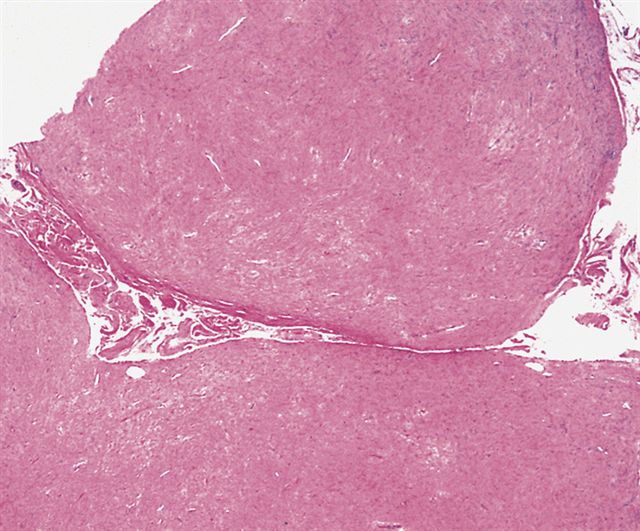

Microscopic (histologic) description

- Well circumscribed tumor of variable cellularity

- Cellularity mostly higher at tumor edges

- Bland spindle cells in a collagenous background

- Tumor has characteristic thin walled slit-like vessels

Microscopic (histologic) images

Contributed by Nasir Ud Din, M.B.B.S.

AFIP images